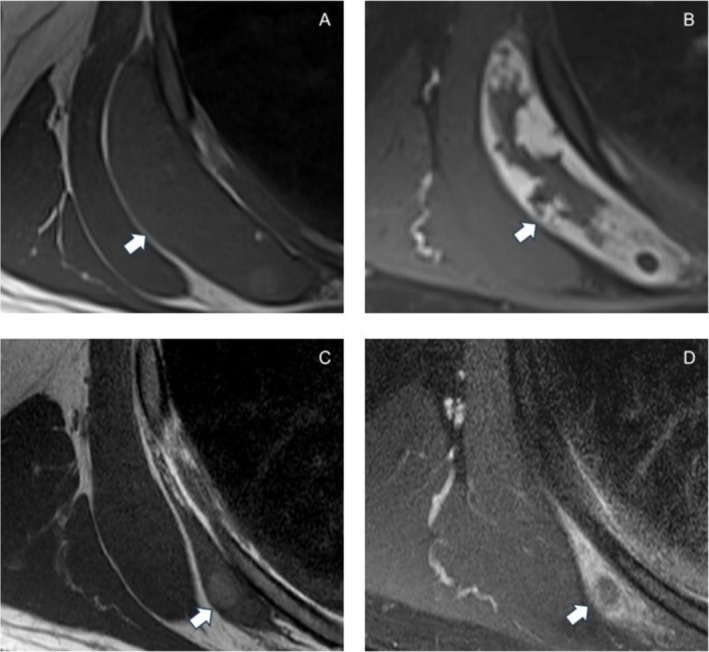

Intravascular papillary endothelial hyperplasia (IPEH) or Masson tumor is a relatively rare benign tumor of vascular origin. While surgical resection is considered standard management, there is limited information regarding its natural history. Given the benign clinical behavior of IPEH, observation may be a viable option, particularly if surgery could incur significant morbidity. We present the case of a patient with a Masson tumor by the chest wall who opted for observation with significant spontaneous decrease in size of his tumor followed by complete resolution over an 18-month surveillance period. This case suggests an alternative approach to surgical resection.